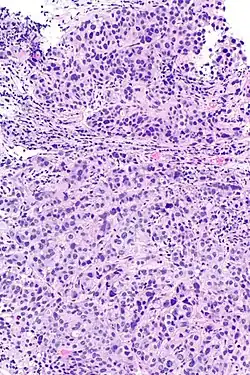

Rak urotelialny pęcherza moczowego, widoczne gniazda komórek nowotworowych

Inwazyjny (naciekający) rak urotelialny jest definiowany jako obecność inwazji nowotworowej poniżej błony podstawnej urotelium[74]. Makroskopowo inwazyjne nowotwory urotelialne mogą przyjmować formę brodawkowatą, polipowatą, guzkową, litą, tworzyć rozlany naciek ściany pęcherza moczowego. Zmiany mogą występować pojedynczo lub wieloogniskowo[75]. Typowo większość guzów pT1 jest brodawczakowata o niskim lub wysokim stopniu złośliwości histologicznej, z kolei guzy o większym zaawansowaniu pT2–T4 wykazują morfologię niebrodawczakowatą i cechują się wysokim stopniem złośliwości[76][77].

Mikroskopowo w utkaniu obecne są komórki tworzące gniazda, sznury komórek lub pojedyncze komórki pooddzielane desmoplastycznym podścieliskiem[76][78]. Możliwy jest bardziej rozlany wzór wzrostu nowotworu, w którym komórki tworzą arkusze, przy czym również w takim utkaniu spotyka się ogniskowo występujące gniazda komórek[78]. Komórki cechują się umiarkowaną do obfitej ilością amfofilnej lub eozynofilnej cytoplazmy i dużym hiperchromatycznym jądrem komórkowym. Jądra komórkowe wykazują znaczną pleomorficzność, nieregularne, kanciaste granice. Liczba i wygląd jąderek wykazuje znaczną zmienność. Gniazda komórek nowotworowych zwykle indukują reakcję desmoplastyczną podścieliska. Obecne są liczne figury mitotyczne i możliwa jest obecność nieprawidłowych figur mitotycznych. W podścielisku większości guzów jest obecny naciek limfocytów i komórek plazmatycznych, naciek najczęściej jest wyrażony ogniskowo od łagodnego do umiarkowanego stopnia, ale może być nasilony i rozlany[76][78]. Może być widoczna inwazja naczyń[78].